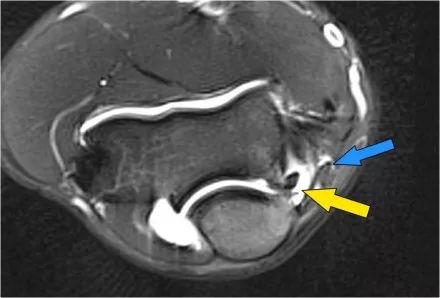

外翻过度综合征的关节病由于外翻过载,在肱骨-尺骨关节的后内侧部分存在剪切力。注意在T1W图像上看到的软骨下硬化(红色箭头)。在T2W图像上存在软骨下骨髓水肿和软骨损失(黄色箭头)。